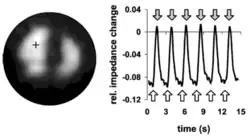

Compared to the conductivities of most other soft tissues within the human thorax, lung tissue conductivity is approximately five-fold lower, resulting in high absolute contrast. This characteristic may partially explain the amount of research conducted in EIT lung imaging.[2] Furthermore, lung conductivity fluctuates during the breath cycle which accounts for the interest of the research community to use EIT as a bedside method to visualize inhomogeneity of lung ventilation in mechanically ventilated patients.[4] EIT measurements between two or more physiological states, e.g. between inspiration and expiration, are therefore referred to as time difference EIT (td-EIT).

Time difference EIT bypasses most of these issues by recording measurements in the same individual between two or more physiological states associated with linear conductivity changes. One of the best examples for this approach is lung tissue during breathing due to linear conductivity changes between inspiration and expiration which are caused by varying contents of insulating air during each breath cycle.[2] This permits digital subtraction of recorded measurements obtained during the breath cycle and results in functional images of lung ventilation. One major advantage is that relative changes of conductivity remain comparable between measurements even if one of the recording electrodes is less conductive than the others, thereby reducing most artifacts and image distortions.[7] However, incorporating a priori data sets or meshes in difference EIT is still useful in order to project images onto the most likely organ morphology, which depends on weight, height, gender, and other individual factors.[29]

In contrast, time difference EIT determines relative impedance changes that may be caused by either ventilation or changes of end-expiratory lung volume. These relative changes are referred to a baseline level, which is typically defined by the intra-thoracic impedance distribution at the end of expiration.[7] Time difference EIT images can be generated continuously and right at the bedside. These attributes make regional lung function monitoring particularly useful whenever there is a need to improve oxygenation or CO2 elimination and when therapy changes are intended to achieve a more homogenous gas distribution in mechanically ventilated patients. EIT lung imaging can resolve the changes in the regional distribution of lung volumes between e.g. dependent and non-dependent lung regions as ventilator parameters are changed. Thus, EIT measurements may be used to guide specific ventilator settings to maintain lung protective ventilation for each patient.[42]